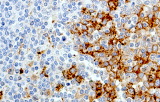

- Linfoma di Hodgkin classico: le cellule tumorali sono tipicamente CD30+ e spesso CD15+, con PAX5 debole e CD20 negativo nelle grandi cellule tumorali.